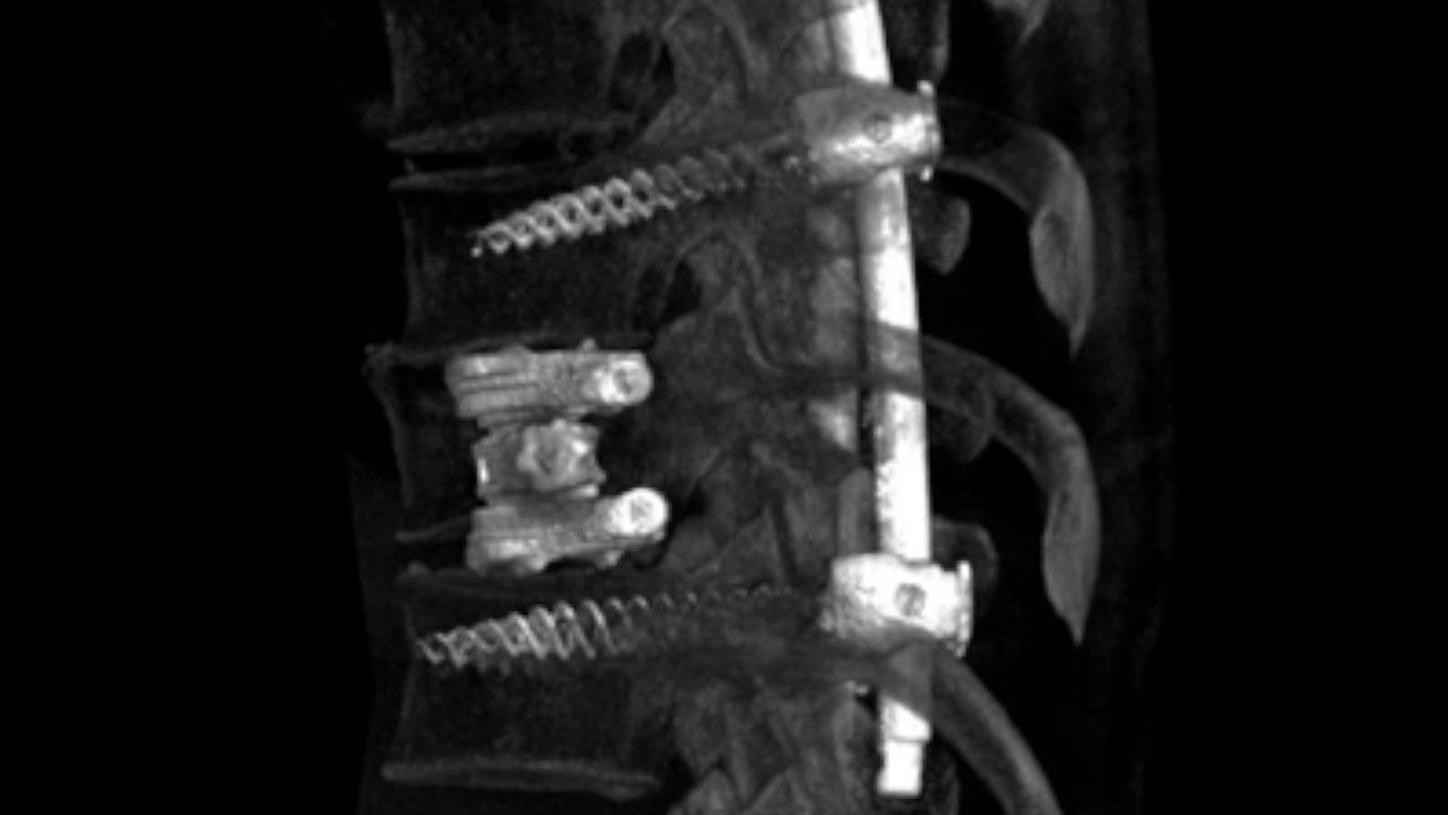

Image-guided therapy can be used to significantly improve a patient’s life by assisting in the treatment of a serious condition, such as a stroke or heart attack. Lower complication rates, faster recovery times, shorter hospital stays, lower risk of disability post treatment, and overall, a better quality of life are just some of the benefits patients can experience with minimally invasive treatment methods.

We’ve made it our mission to keep pushing boundaries and driving possibilities. That is why we offer image-guided workflows for various clinical disciplines, including interventional radiology, cardiology, and surgery.